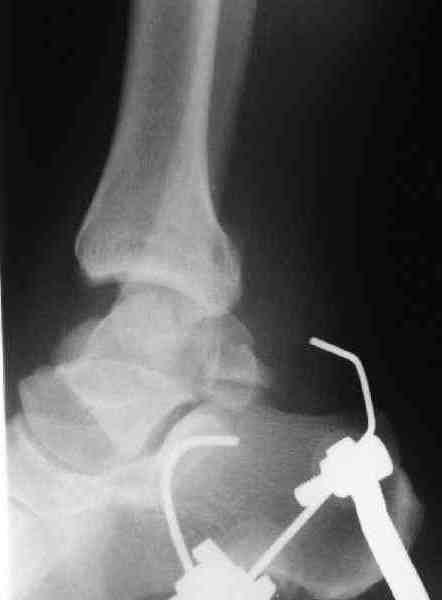

Re: повреждение таранной кости

повторили рентгенограммы и доделали проекции, к единому мнению все еще не пришли